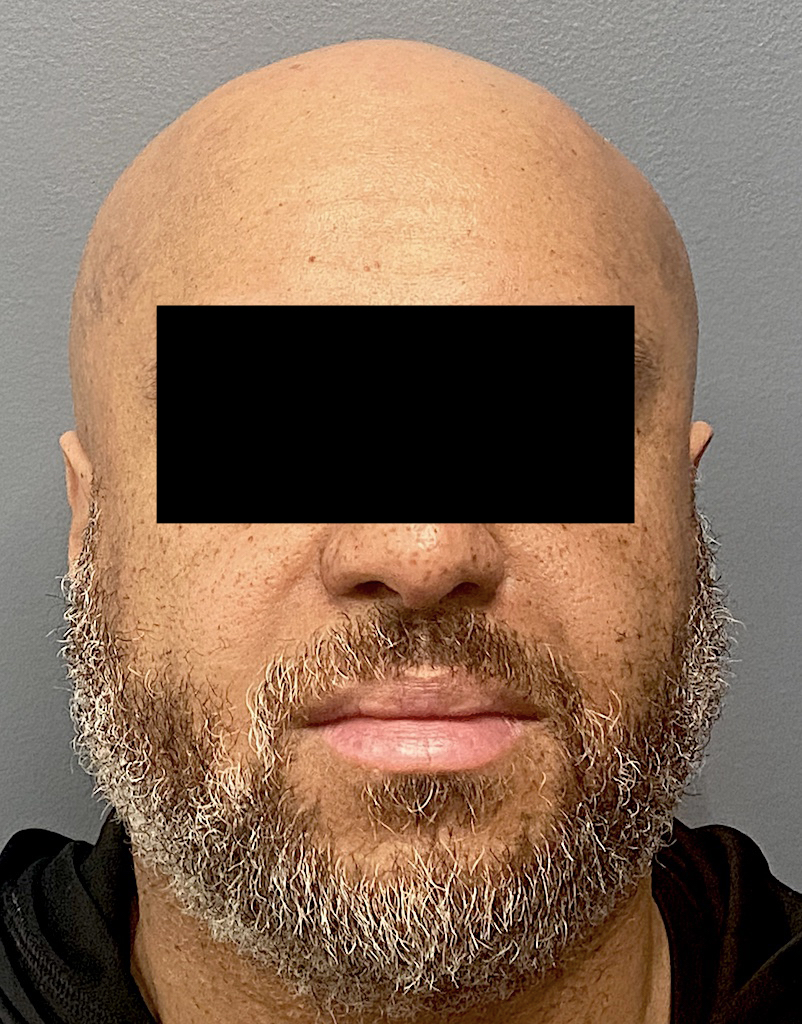

Patient 61

Desire for less wide sides of the head.

Head narrowing surgery performed by removal of posterior temporal muscle through postauricular incisions.

Desire for less wide sides of the head.

Head narrowing surgery performed by removal of posterior temporal muscle through postauricular incisions.